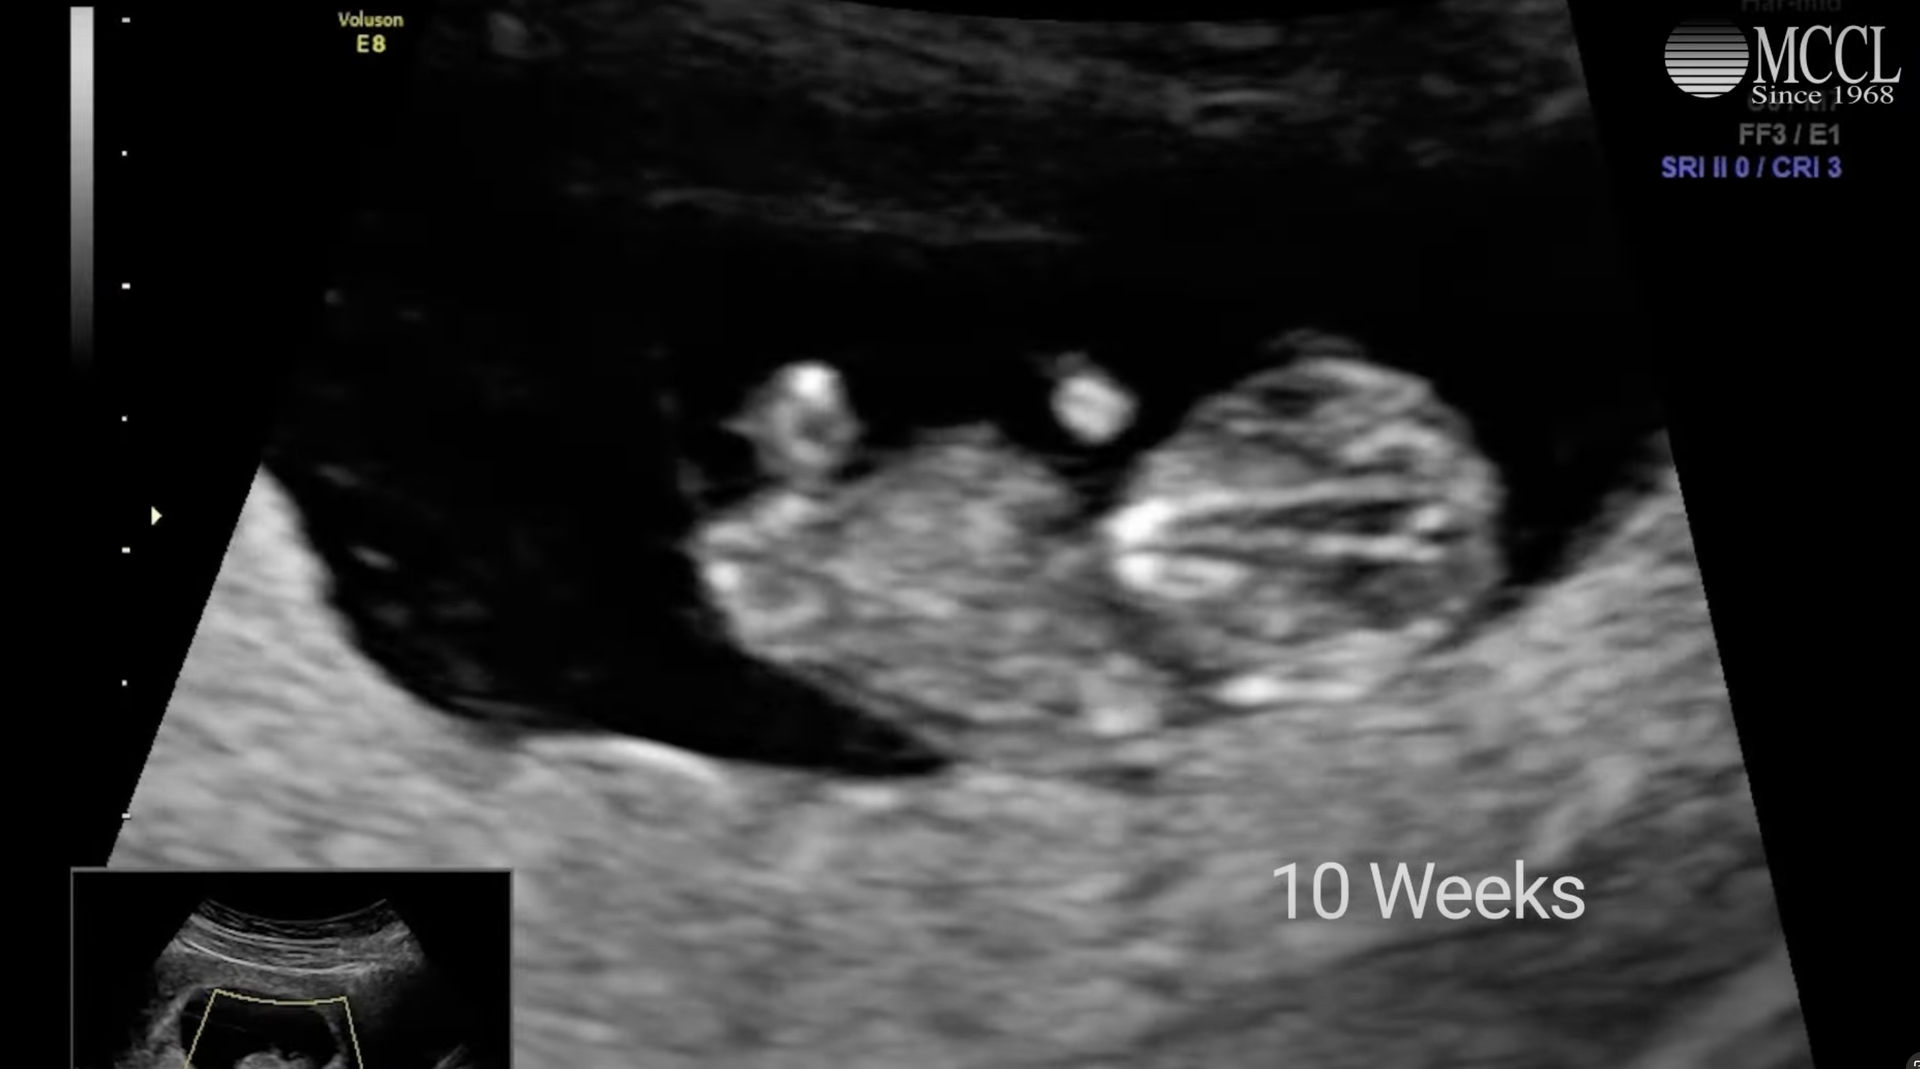

Video: The Reality of Abortion in Our State

Via MCCL

Watch this powerful video by our allies at MCCL that highlights the abortion extremism in our state laws.

Watch Now